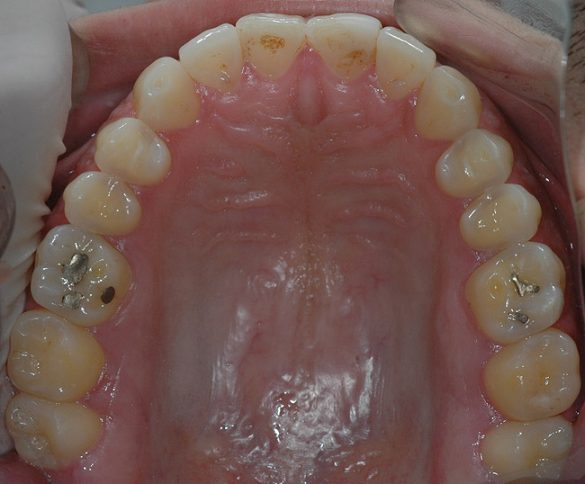

În cursul examinării clinice s-a notat o igienă orală satisfăcătoare. Pacientul prezenta coroziunea suprafeţelor ocluzale şi orale la dinţi maxilari şi mandibulari posteriori (fig. 1). Avea, de asemenea, arii expuse de ţesut dentinar (fig. 3) şi restaurări din amalgam compromise în lipsa sprijinului adecvat.